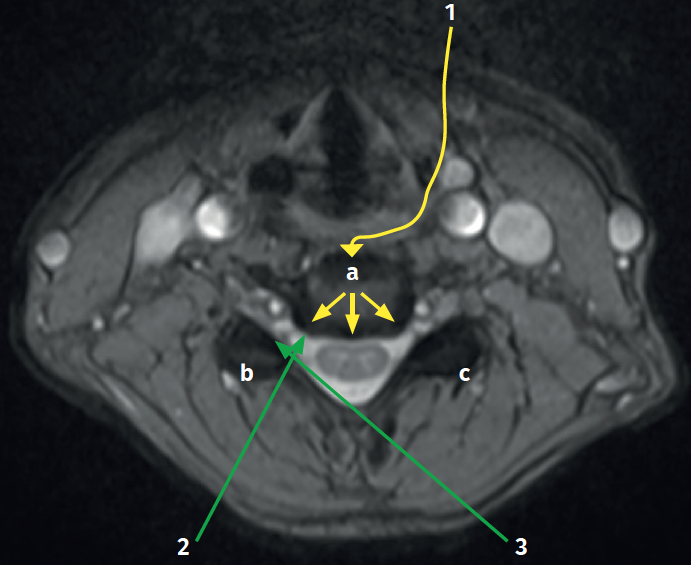

Figure 10. The different endoscopic approach options in the cervical spine. As can be seen, both are described, anterior and posterior. a: endoscopic anterior cervical approach; b: endoscopic posterior cervical approach, single-portal ipsilateral / foraminal; c: endoscopic posterior cervical approach, single-portal bilateral; 1: endoscopic anterior cervical approach; 2: single- or two-portal unilateral; 3: single- or two-portal bilateral.